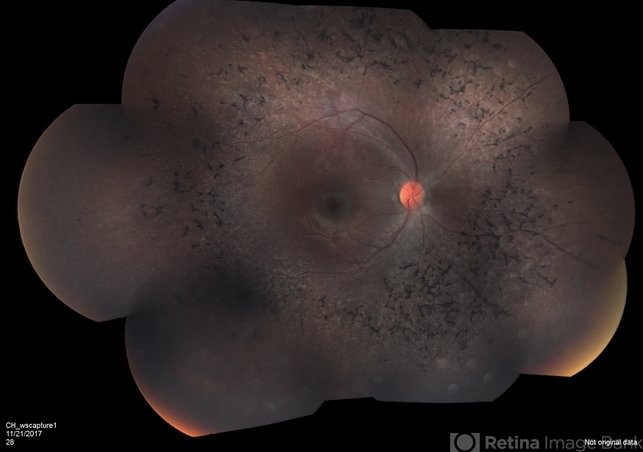

- retinitis pigmentosa

- Fundus camera

- Retinitis pigmentosa.